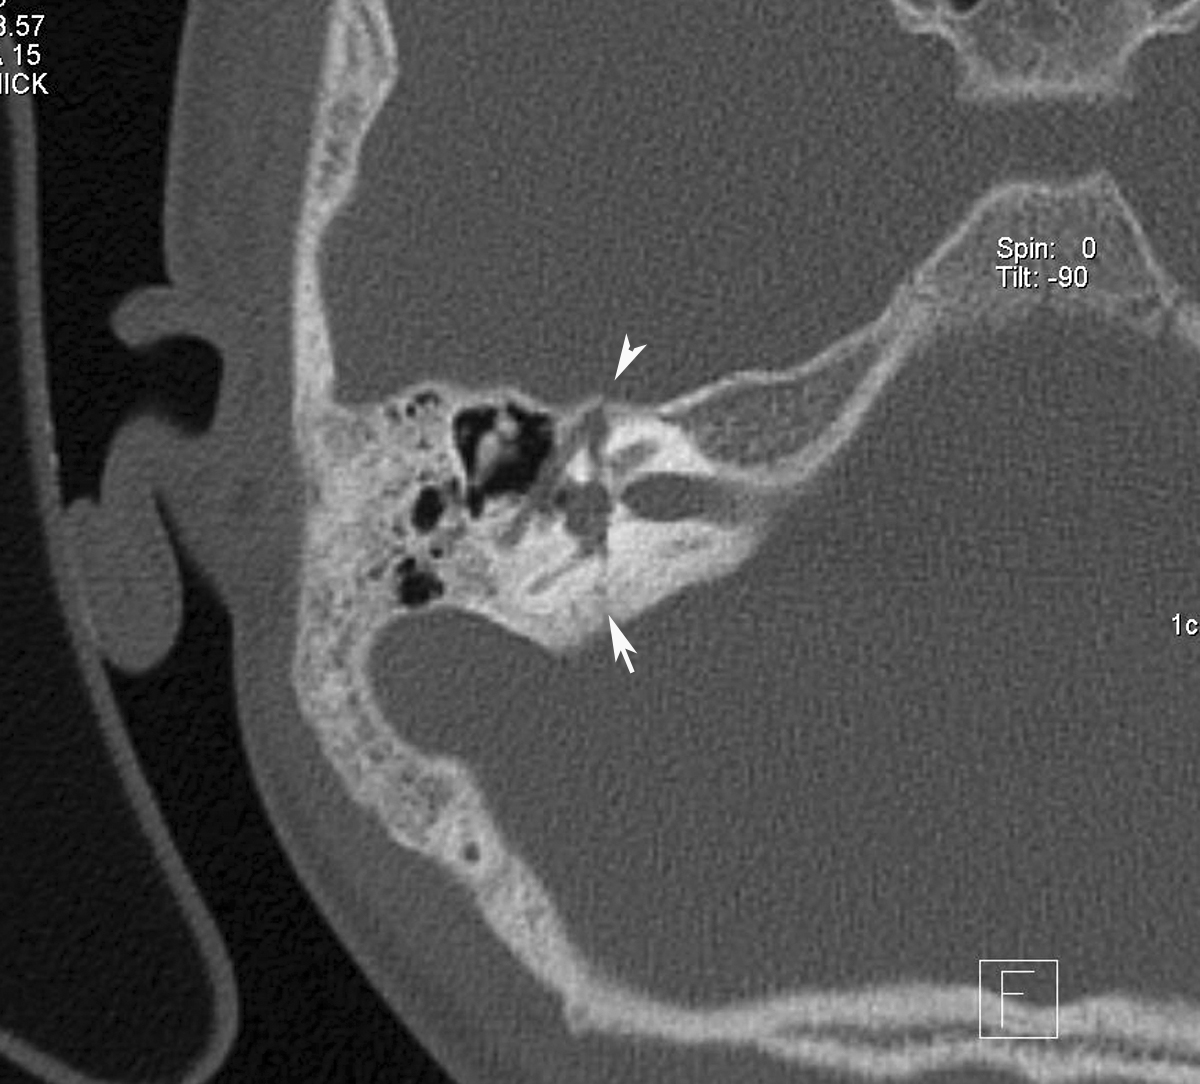

HRCT of right temporal bone axial image showing transverse temporal bone fracture (arrow) and the fracture line passing through the first anterior genu of the facial nerve canal (arrow head).

Subsequent section of the HRCT right temporal bone showing the fracture passing through the facial nerve canal (arrow head).

HRCT: can demonstrate a lucency through the temporal bone. Involvement of the middle ear, petrous bone, otic capsule, and facial nerve canal are the primary determinants of prognosis.